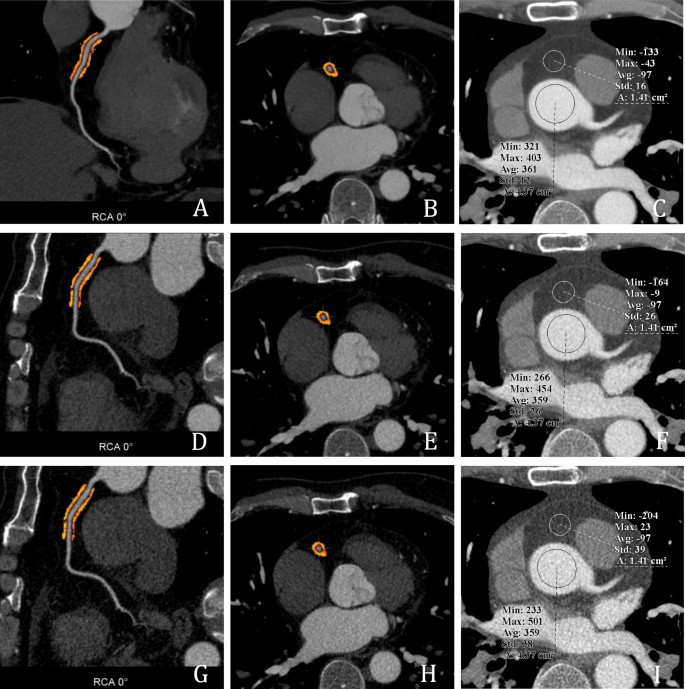

For images of the same patient reconstructed using different algorithms (DLIR-H, ASiR-V50%, and FBP), the attenuation value ± standard deviation was measured at the level of the aortic root, aligned with the ostium of the left main coronary artery. The measured attenuation value was regarded as the mean coronary artery attenuation, while the standard deviation was used as an indicator of image noise in CCTA. The measurement procedure involved ensuring consistency in both the position and size of the ROI using the Clone function. The measurement area was set to 2/3 of the largest cross-sectional area of the vessel, avoiding the vessel wall, as well as calcified and non-calcified plaques. Each measurement was repeated three times, and the average value was taken, as shown in Fig. 1.

Schematic of coronary FAI, image noise, and pericardial fat attenuation measurements. (a–c) show CCTA images reconstructed using the high-level deep learning image reconstruction (DLIR-H) algorithm. Figure displays the longitudinal diameter fat attenuation index (FAI) of the proximal right coronary artery (RCA) segment (10–50 mm), with an FAI value of − 92 HU. (b) shows the corresponding short-axis FAI. (c) demonstrates an image noise level of 12 HU and a pericardial fat attenuation value of − 97 HU at the level of the left main coronary artery. (d–f) present CCTA images reconstructed using the adaptive statistical iterative reconstruction-Veo at a level of 50% (ASiR-V50%) algorithm. (d) shows the longitudinal diameter FAI of the proximal RCA (10–50 mm), and (e) shows the short-axis FAI, with an overall FAI of − 95 HU. (f) displays image noise of 26 HU and a pericardial fat attenuation value of − 97 HU. (g–i) illustrate CCTA images reconstructed using the filtered back projection (FBP) algorithm. (g) shows the longitudinal diameter FAI of the proximal RCA (10–50 mm), and (h) the short-axis FAI, with an FAI value of − 97 HU. (i) demonstrates image noise of 38 HU and a pericardial fat attenuation value of − 97 HU.

Measurement of pericardial fat attenuation values for different reconstruction algorithms

For images of the same patient obtained using different reconstruction algorithms (DLIR-H, ASiR-V50%, and FBP), the attenuation value of the pericardial adipose tissue in front of the aortic root was measured at the level of the opening of the left main coronary artery. The measurement method involved ensuring consistency in both the position and size of the ROI using the Clone function. The measurement area was defined as the maximum fat area, with the measurement avoiding blood vessels and adjacent myocardial tissues. Each measurement was repeated three times, and the average value was taken, as shown in Fig. 1.

Coronary CTA image analysis

CCTA image analysis was performed using axial views and curved planar reformation (CPR) to evaluate the proximal 40 mm segments of the left anterior descending artery (LAD) and left circumflex artery (LCX), as well as the 10–50 mm segment of the right coronary artery (RCA); these are collectively referred to as the proximal 40 mm of the three major coronary arteries.To avoid the potential influence of the aortic wall on the RCA, the analysis for the RCA was limited to the 10–40 mm segment4. See Fig. 1.